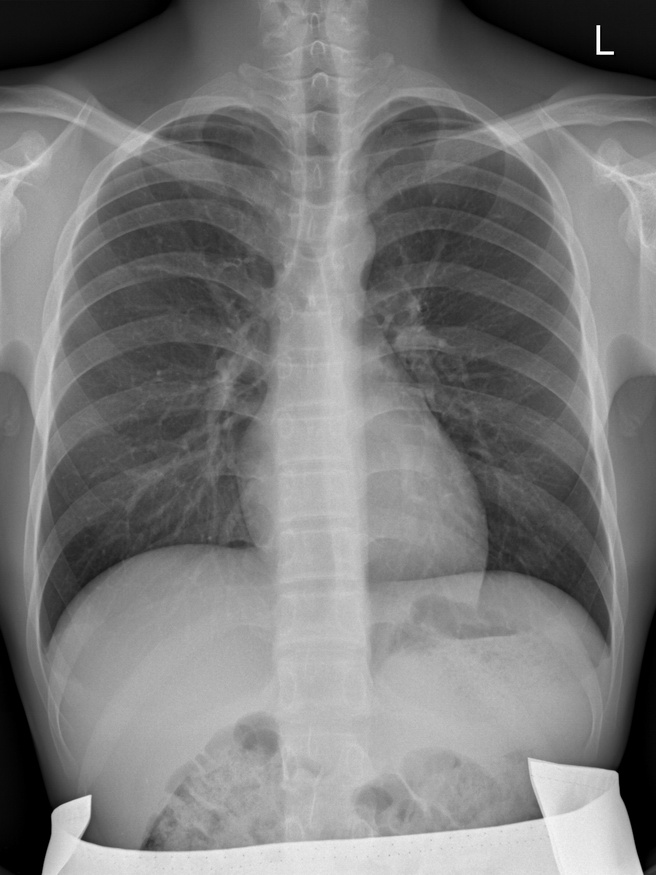

胸部正侧位平片

我们看到图像中,骨骼、肺组织等组织能形成较好的对比,利于医生诊断,X线的优点是辐射剂量小,操作简单快捷、价格便宜。而我们也可以注意到,这个图像是许多组织重叠在一起成像,无法区分前后组织之间的关系以及反映各自的密度与厚度。这是X成像的缺点。